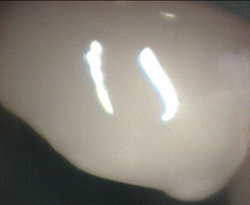

Back of front tooth